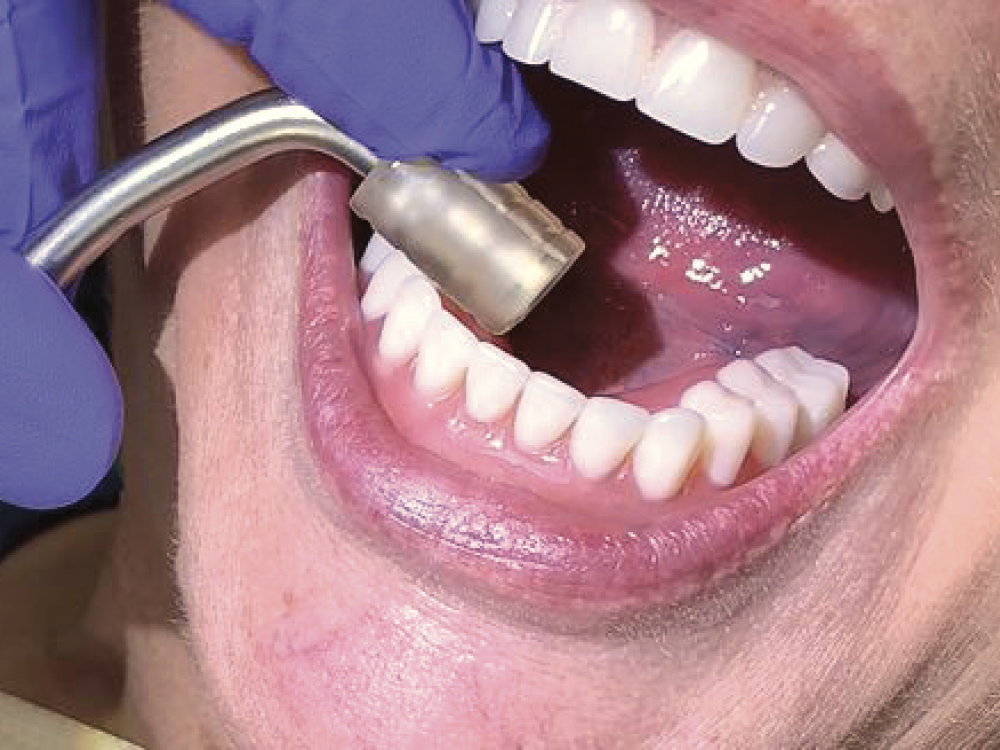

Occlusion, esthetics and phonetics were checked and approved by both the patient and the dentist. The patient was given instructions for cleaning the appliance using a water irrigation system and a toothbrush with toothpaste. The irrigation device provides for effective removal of debris and bacteria on all surfaces of the appliance but especially the traditional hard-to-clean intaglio surfaces. Because hygiene maintenance is often a neglected part of patient instruction for this type of full-arch restoration, the patient received in-depth instruction on how to clean daily with special emphasis on usage of the irrigation device. Water irrigation systems should be dispensed to all full-arch fixed prosthesis patients and considered mandatory in order to prevent the accumulation of debris under the prosthesis.